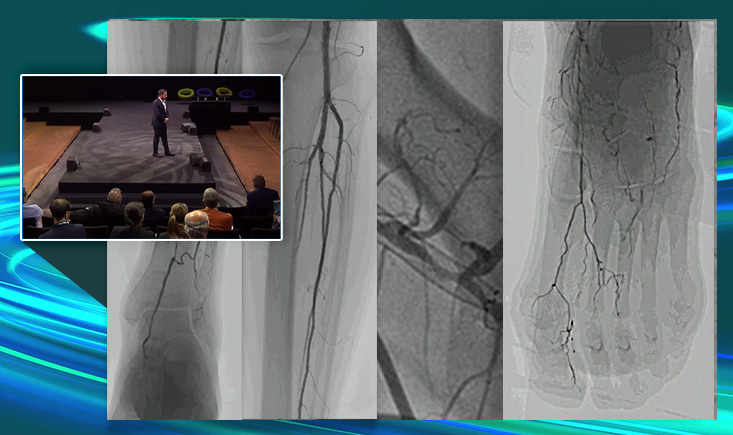

Get expert tips for below-the-ankle access, explore a smart algorithm to guide intraluminal re-entry, and learn how to master wire escalation for CTOs. Discover the best tools for optimal vessel preparation before stenting or DCB, and find out what to do when the wire crosses the lesion… but nothing else moves forward.